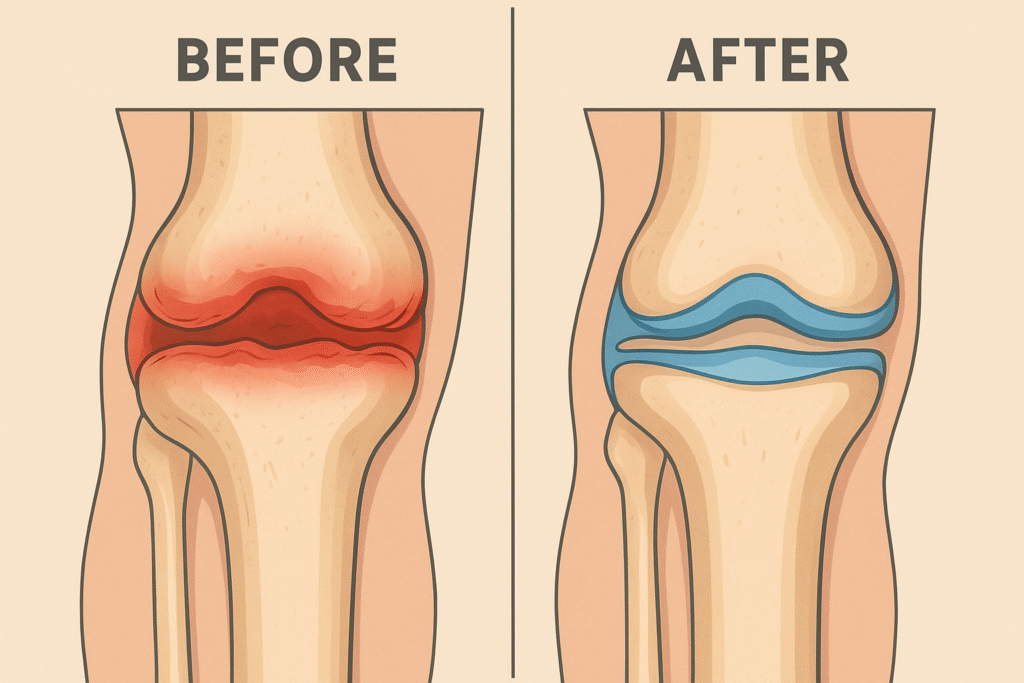

Joint Genesis is a natural dietary supplement created to support joint health and flexibility. It’s specially designed to fight age-related joint stiffness by targeting the root cause of joint discomfort—the decline of hyaluronic acid and synovial fluid.

Instead of masking the pain, it helps restore lubrication and cushioning in the joints, which means smoother movements and less discomfort over time.